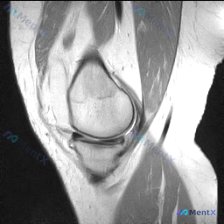

刚整理了一个挺有启发的病例,分享给大家一起讨论。 病例核心信息 - 核心疑问:患者主诉提示存在半月板异常,提供单张膝关节矢状位T1加权磁共振影像供分析 - 影像读片结果: 1. 骨骼:股骨远端、胫骨近端、髌骨骨皮质连续,骨髓信号未见异常 2. 半月板:形态完整,呈均匀低信号,未见高信号穿透关节面,无...